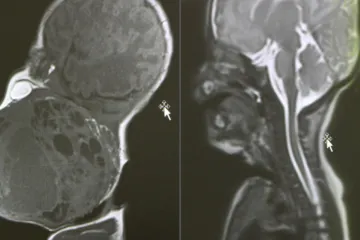

NEVJEROJATAN ZAHVAT / Hrvatski liječnici napravili čudo: Bebi usred porođaja izvadili tumor veličine glave